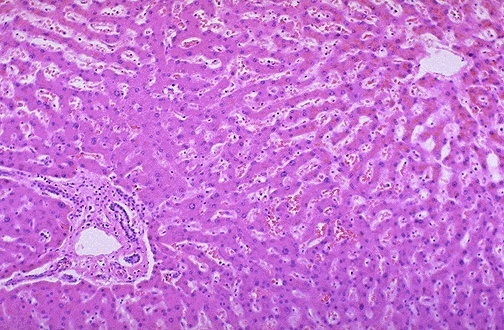

肝脏之所以再生,是因为肝细胞再生能力极强。肝脏是由肝细胞组成,肝细胞极小,肉眼看不到,必须通过显微镜才能看到。人肝约有2000亿个肝细胞,组成约有50万个肝小叶,由肝小叶组成左右两半(右叶占全肝的60%),分为五叶(左叶、左旁中叶、尾叶、右旁中叶、右叶)和八段。

图2 正常人的肝脏是由肝细胞组成的肝小叶构成的

当肝脏受物理化学因素损伤或部分切除时,肝实质细胞能迅速反应。肝小叶各部位肝细胞增殖反应速度不同。进来研究发现,骨髓细胞可以到肝脏分化成肝细胞,这样就为肝细胞再生提供了新的途径。

图6 硬化肝脏显微镜下的表现(与图2比较看就明显不同了)